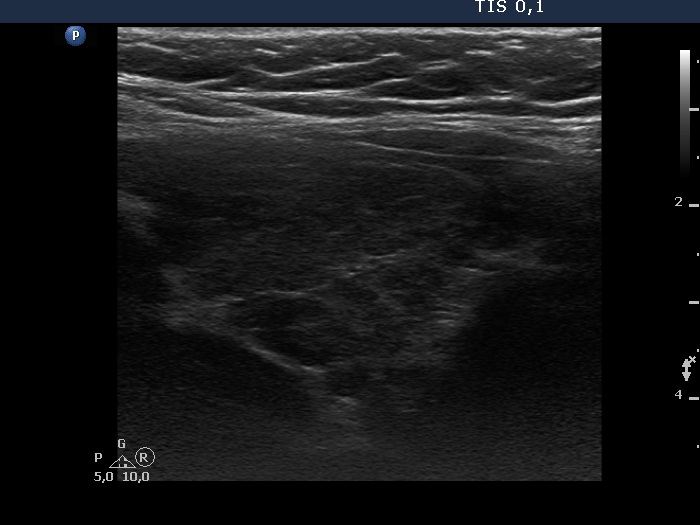

Consecutive patients with the final diagnosis of Hashimoto's thyroiditis - case 9 (348) (ultrasonographic picture 5)

Left lobe, longitudinal scan.